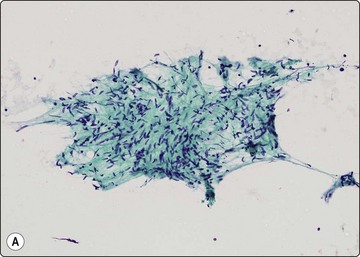

Gastrointestinal stromal tumors (GISTs), formerly classified as smooth muscle tumors, have now been extracted as a distinct entity. They are mesenchymal tumors, arising in the wall of the gastrointestinal tract, showing a spectrum of benign, borderline and malignant behavior. They are typically spindled but there is also an epithelioid variant showing the same antigen profile. Cytodiagnosis of the spindle-celled variant is relatively simple, showing fascicles of spindled cells with elongated, cigar- or comma-shaped nuclei, often set in a wispy filamentous background (Fig. 11.22A and B). The epithelioid variant presents greater difficulty, resembling epithelial tumors. The cells are round, cytoplasm distinct with a perinuclear halo, and nuclei vesicular (Fig. 11.22C). The tumors express CD117 (C-kit) and CD34 (Figs 11.23 and 11.24), but are negative for desmin, S-100 and keratin. Cytopathologists must be ‘GIST-conscious’ owing to the responsiveness of these tumors to Gleevec, which can induce tumor regression and long-term response, even in metastases.132-136

image image

Fig. 11.22 Gastrointestinal stromal tumor (GIST)

(A, B) Spindle cell variant; typical pattern (A, Pap, LP; B, MGG, IP); (C) Epithelioid variant (MGG, HP).